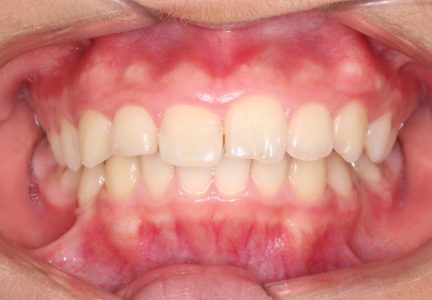

État final

Résultats obtenus

- Relation de Classe I obtenue

- Guidage fonctionnel des canines des deux côtés

- Surplomb et recouvrement normaux obtenus

- Supraclusion améliorée

- Surplomb amélioré

- Amélioration significative du recouvrement

- Amélioration significative du surplomb

- Lignes médianes coïncidant

- Inclinaison axiale correcte des incisives

- Courbe de Spee nivelée

- Arcades alignées et coordonnées

- Forme de l'arcade améliorée

- Ligne de sourire esthétique obtenue

- Cas où tous les objectifs de traitement ont été atteints

- Arcades harmonieuses obtenues